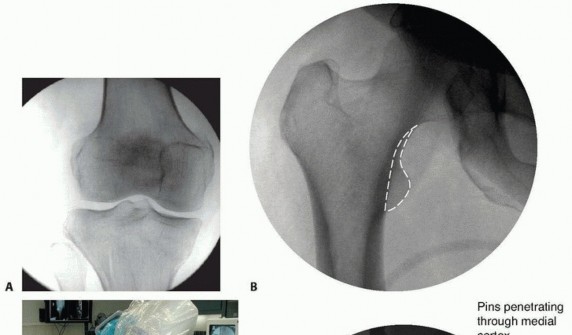

### FIG 3 • A. Patient with a grade IIIA open distal femur with extruded fragment; the “extension” of the femoral condyles is outlined. B. Patient with a distal femur fracture with intercondylar extension showing the subtle rotational deformities of the individual condyles. C. The muscle forces are shown on the distal femur, as is the femoral artery and vein entering the canal of Hunter (arrow). The adductor magnus inserts on the adductor tubercle, leading to a varus deformity of the distal segment. D. A lateral image of the same patient with the popliteal artery and tibial nerve drawn in to show the relative proximity to the fracture ends. 468

### FIG 10 • A,B. AP and lateral radiographs of an elderly patient with multiple comorbidities with an extra-articular distal femur fracture (AO type A; an incomplete intercondylar split— red dashed arrow). C,D. Postoperative radiographs showing stabilization with retrograde intramedullary nail. E,F. One-year postoperative radiographs showing a healed fracture with some subsidence of the metaphyseal region and mild protrusion of hardware through the notch. Ninety-five-degree condylar screw Ninety-five-degree blade plate Nonlocking plates with or without medial support (medial plate or external fixation) Limited internal fixation Limited fixation with screws only can be used for partial articular type B, especially type B3. The amount of open reduction required depends on the adequacy of closed reduction techniques and obtaining an anatomic reduction of the joint surface. Headless screws are useful for type B3 fractures in which the screws have to penetrate the joint surface ( FIG 12). Countersinking the screw heads can also be performed. Biomechanics of fixation: implant considerations There has been concern that the newer locking plate constructs are too stiff, resulting in inconsistent and asymmetric callus formation. 9 Some clinical evidence show less callus formation with stainless steel plates versus titanium plates. 9 Conversely, a biomechanical study has not shown a significant difference mechanically between constructs of stainless steel LISS plates with bicortical screws or titanium LISS plate with unicortical screws.1 474

--- - FIG 12 • A. Lateral radiograph of patient with a grade II open distal medial femoral condyle fracture (type B3). The Hoffa fragment is outlined. B. Postoperative radiograph after fixation with headless screws, buried underneath the subchondral bone. Soft tissue dissection should be limited. Adequate exposure is important to anatomically restore the articular surface. Restoration of limb “anatomy” must be accomplished and allow early range of motion. Stable internal fixation and length and sizes of implants should be templated. Radiographs of the injury can be templated with implant templates to ensure that proper lengths are available. A tentative plan of the fixation construct can be drawn on the image. Additionally, “preop planning” of the operating room should be performed; this includes a discussion with the operative team about the positioning and equipment needed for the procedure. The need for bone grafting or the use of bone graft substitutes should be assessed. Fracture fragments and the anticipated fixation construct should be templated. The surgeon should check for coronal plane fractures of the condyles (also known as Hoffa fragments) (see FIGS 5C and 6). 476